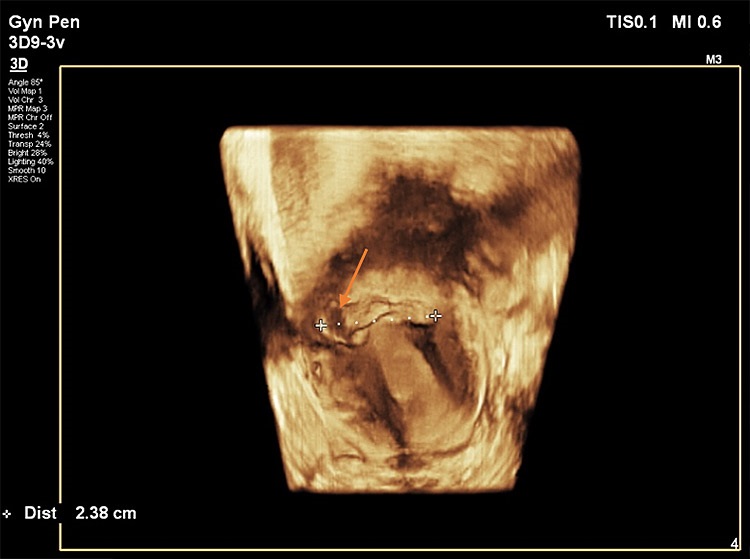

Στις παρακάτω εικόνες από ενδοκολπικό υπέρηχο φαίνονται παραδείγματα επιπέδου τρία προηγμένης τεχνολογίας υπερηχογραφικής μελέτης όπου σημαντικές λεπτομέρειες σε ό,τι αφορά τη θέση, το μέγεθος και την ανατομική συσχέτιση της Ισθμοκήλης, είναι εμφανή με καθαρό τρόπο, επιτρέποντας την εκτίμηση κατά πόσο μπορεί να γίνει χειρουργική επέμβαση ή όχι, και αν ναι με ποια τεχνική. Όλες οι εικόνες έχουν παραχθεί με υπερηχογραφική μηχανή Philips Elite, Costas Panayotidis operator.

Εικόνα 2. Εδώ φαίνεται η υπερηχογραφική τρισδιάστατη μελέτη που δείχνει την ετερογένεια ισθμοκήλης η οποία τείνει να επεκτείνεται πλάγια και διαγώνια προς στο κάτω δεξιό τμήμα της μήτρας